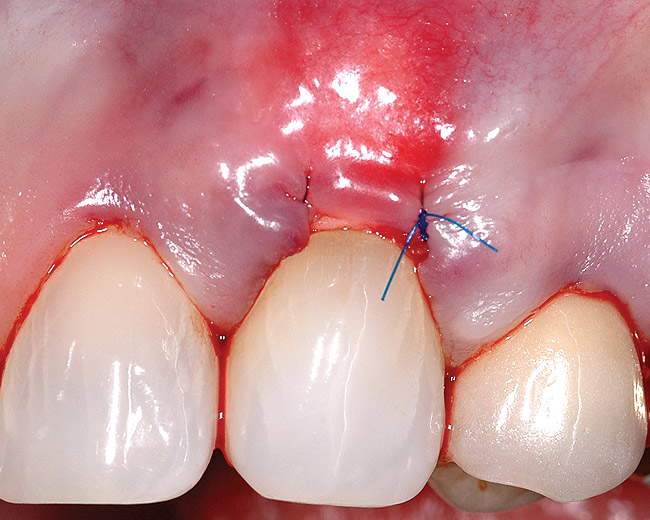

Fig 6. After insertion into the pouch, the allograft and pouch margin were advanced to completely cover the root and secured with a 6-0 polypropylene sling suture.

Figure 6